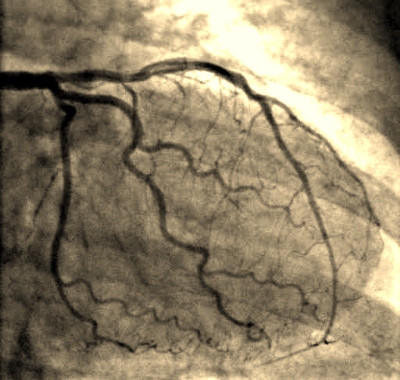

Standing at my right side he presses the top of my leg in the groin area, looking for a pulse, I think, during which I repeat how terrified I am. After the incision, the tube containing the wire goes in and after that all I can hear is the doctor explaining to the other doctor exactly what's happening on the screen. At one stage I quickly glance at the monitor to see the wire moving up my artery which very quickly makes me look away again.

Every so often I'm asked to take a deep breath but I can't hold it for long. At one point I hear something about a narrowing on the left which I assume is in the artery. Towards the end the doctor tells me he is going to flood my heart with a warm eye which sounds very scary indeed! The sensation is really strange because I can feel the warm liquid whooshing up all through my chest. He then flushes it through and it's all over. I'm so cold.

Decide to ask him what he found and he explains that 40% of my left artery has narrowed and that most likely I will be put on medication which doesn't sound too life threatening. While moving over onto the trolley, with tube still in situ, I have to keep my right leg straight which I think is to prevent bleeding but I can't stop shivering and shaking. I'm then moved into recovery.

In June of this year I had a heart CT scan which showed my heart still to be in great working order but most amazingly, the 40% blockage which showed up eight years ago on the angiogram is now totally disappeared! It has to be the Lipostat. The Consultant in the hospital suggested I should be taking 10mg but because of my normal cholesterol level and above all, the fear of getting the shoulder and arm pain back, I've decided to continue with the 5mg dose.

Above image via: www.healthdirect.co.uk

Bottom angiogram image via: www.heart-valve-surgery.com